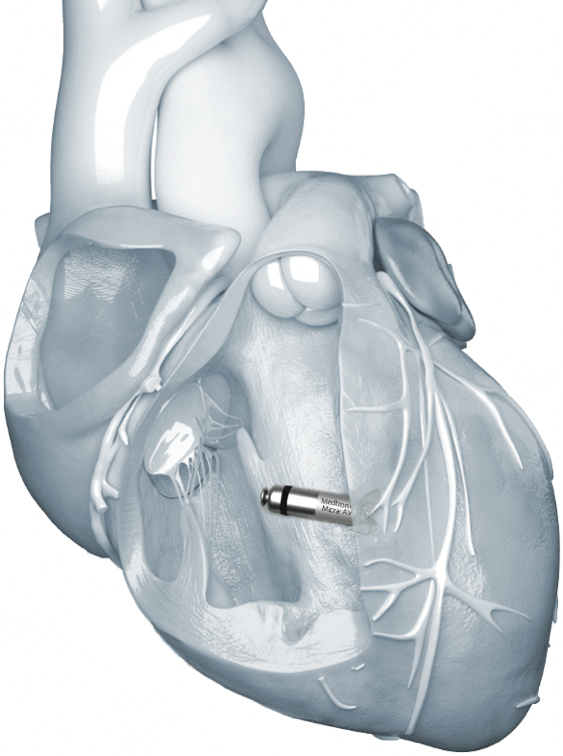

무전극선 심박동기(Leadless Pacemaker)란 비타민 크기 초소형 기기 안에 배터리와 센서, 회로를 집약해 심장 내부에 바로 이식할 수 있도록 만들어진 심박동기다.

피하 주머니를 만들어 별도 배터리를 삽입하거나 전극선을 연결하지 않고도 독립적으로 박동 조절을 제공한다.

메드트로닉은 지난 2015년 기존 심박동기 대비 10분의 1 수준인 2.6cm 크기 마이크라를 선보이며 무전극선 심박동기 시대를 열었다.